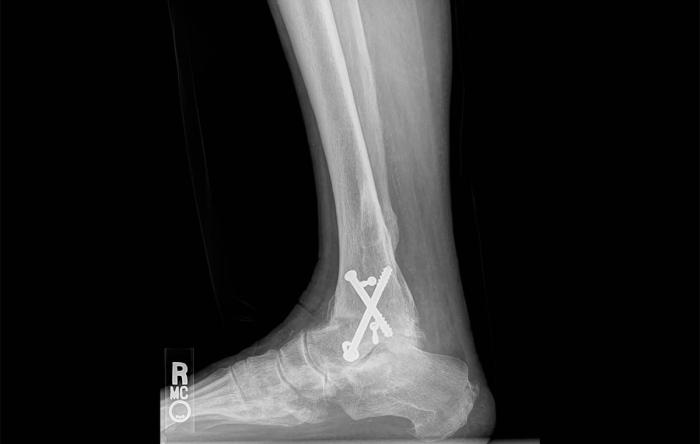

Aging bodies don’t crash well. The time out, the pain, the stiffness, and the cost of the injuries in downtime and missed work become more brutal, more of a threat to survival. The key to continuing to surf—along with engaging in other highly active sports—is judgment.